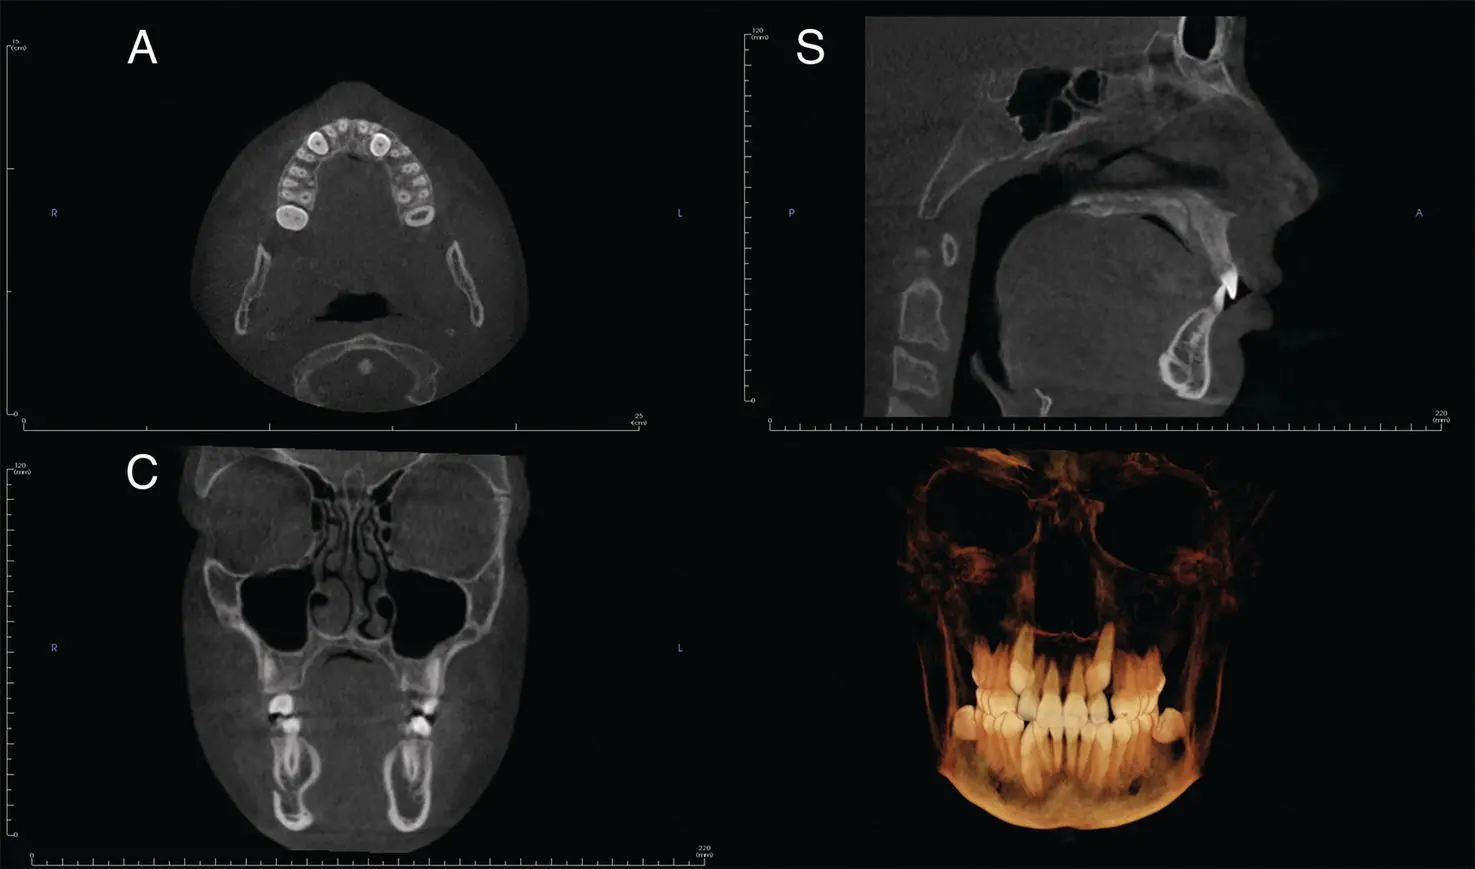

Figure 1.4.Axial (A), coronal (C), sagittal (S), and reconstructed 3D views from medium FOV.